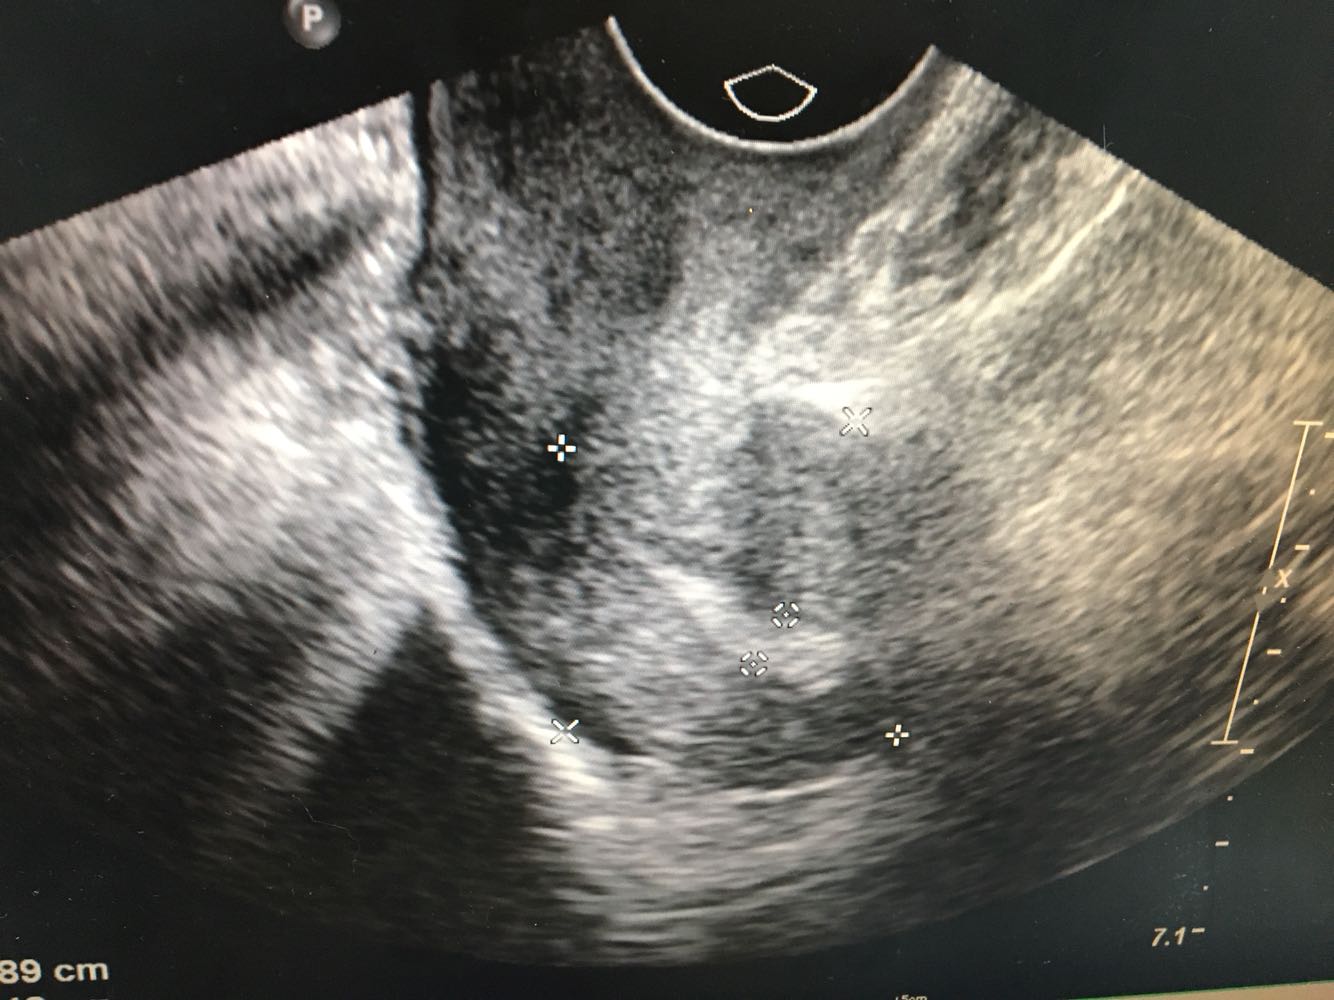

妇科检查:外阴:未见异常;阴道:畅,少量白色分泌物;宫颈:肥大,光滑;宫体:前位,如正常大小,无压痛,活动度好,双附件:未触及异常。        辅助检查:【妇科B超】现子宫肌层回声尚均匀,内膜厚9 mm,回声不均匀,双侧卵巢未显示,盆腔内未见明显异常血流信号,提示子宫内膜增厚不均。 行手术治疗。

诊断:  1、绝经后出血;2、子宫内膜增厚(性质待定) 诊疗方案:患者入院后完善各项检查,今全麻下行腹腔镜下宫腔镜子宫内膜活检+宫腔赘生物摘除+宫腔镜下刮宫 。切除赘生物3枚,分别取出送病理。宫腔镜下沿宫腔四壁搔刮,无明显组织刮出。手术顺利。术后给予抗炎治疗,观察阴道出血少,生命体征平稳,准予出院。